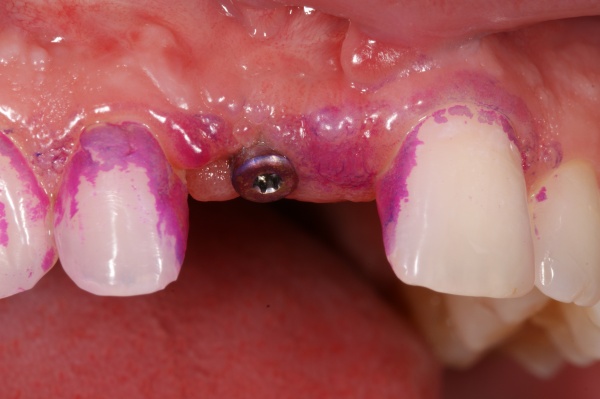

Bei vielen Patienten liegt der Zahnverlust in der parodontalen Erkrankung, oft auch kombiniert mit weiteren Risikofaktoren, begründet. Analog zur Parodontitis können auch die periimplantären Gewebe eine Entzündung zunächst im Sinne einer Mukositis (s. Abb. 1) und dann einer Periimplantitis (s. Abb. 2) entwickeln. Dieses Risiko ist bei Patienten mit einer vorherigen parodontalen Erkrankung erhöht, sodass zunächst auf die Fragestellung eingegangen werden soll, ob in einem parodontal kompromittierten Gebiss eine Implantation statthaft ist. Wie bereits erwähnt, handelt es sich bei der Parodontitis um eine durch die Mikroorganismen des oralen Biofilms (s. Abb. 3) verursachte Entzündung. In diesem Zusammenhang sind einige mikroanatomische Abweichungen der periimplantären Gewebe im Vergleich zum Parodontium des natürlichen Zahnes bedeutsam. Unterschiede zeigen sich vor allem in der Struktur der periimplantären Mukosa. Während die dentoalveolären und gingivalen Faserbündel der marginalen Gingiva nach lateral, koronal und apikal ausgerichtet sind, ziehen diese Faserbündel am Implantat (parallel zur Implantatoberfläche. Sie enthalten zudem mehr Kollagen, weisen aber weniger der für Reparaturvorgänge wichtigen Fibroblasten auf. Zudem ist die Gefäßversorgung in der periimplantären Mukosa im Vergleich zum natürlichen Parodont reduziert. Daraus resultiert eine erhöhte Anfälligkeit der periimplantären Gewebe bei einer Exposition mit den Keimen des oralen Biofilms. In der frühen Phase der dadurch ausgelösten entzündlichen Reaktion gibt es zwar keine Unterschiede, bei fortwährender Exposition kommt es jedoch am Implantat zu einem tieferen Vordringen der entzündlichen Läsion und zu einer rascheren Beteiligung des Alveolarknochens. Dementsprechend darf eine Implantation erst nach entsprechender parodontaler Sanierung und keinesfalls in eine Mundhöhle mit bestehender, unsanierter Parodontitis hinein erfolgen. Die Frage, ob in ein parodontal saniertes Gebiss hinein eine Implantation erfolgen darf, wurde lange kontrovers diskutiert. Inzwischen gibt es einen wissenschaftlich evident abgesicherten Konsens, dass die Implantation im parodontal sanierten Gebiss statthaft ist. Einige Punkte verdienen dabei jedoch besondere Beachtung: